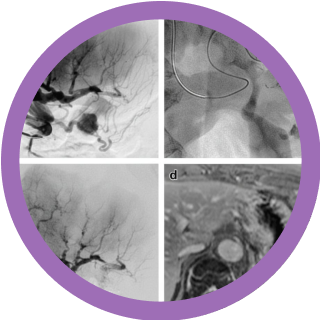

La embolización vascular es un procedimiento de radiología intervencionista que se utiliza para bloquear o reducir el flujo sanguíneo en vasos específicos. Este tratamiento se realiza de forma mínimamente invasiva, insertando un catéter en una arteria o vena y guiándolo hasta la zona que se desea tratar. Una vez en el lugar correcto, se inyectan agentes embolizantes para ocluir el vaso.

Los cianoacrilatos son los principales adhesivos líquidos utilizados en las intervenciones endovasculares y desempeñan un papel fundamental en el manejo de las anomalías vasculares, las hemorragias y muchas enfermedades vasculares. Solo pueden inyectarse en forma de mezcla con aceite etiodizado (Lipiodol), que aporta radiopacidad y modula la velocidad de polimerización.

El objetivo de esta presentación es ofrecer una visión general de las principales indicaciones clínicas de las inyecciones endovasculares de NBCA, tales como la embolización arterial (MAVs periféricas, reducción tumoral preoperatoria, hemostasia), la embolización venosa (de la vena porta, venas gonadales o várices) y la embolización percutánea, así como sus resultados y complicaciones.